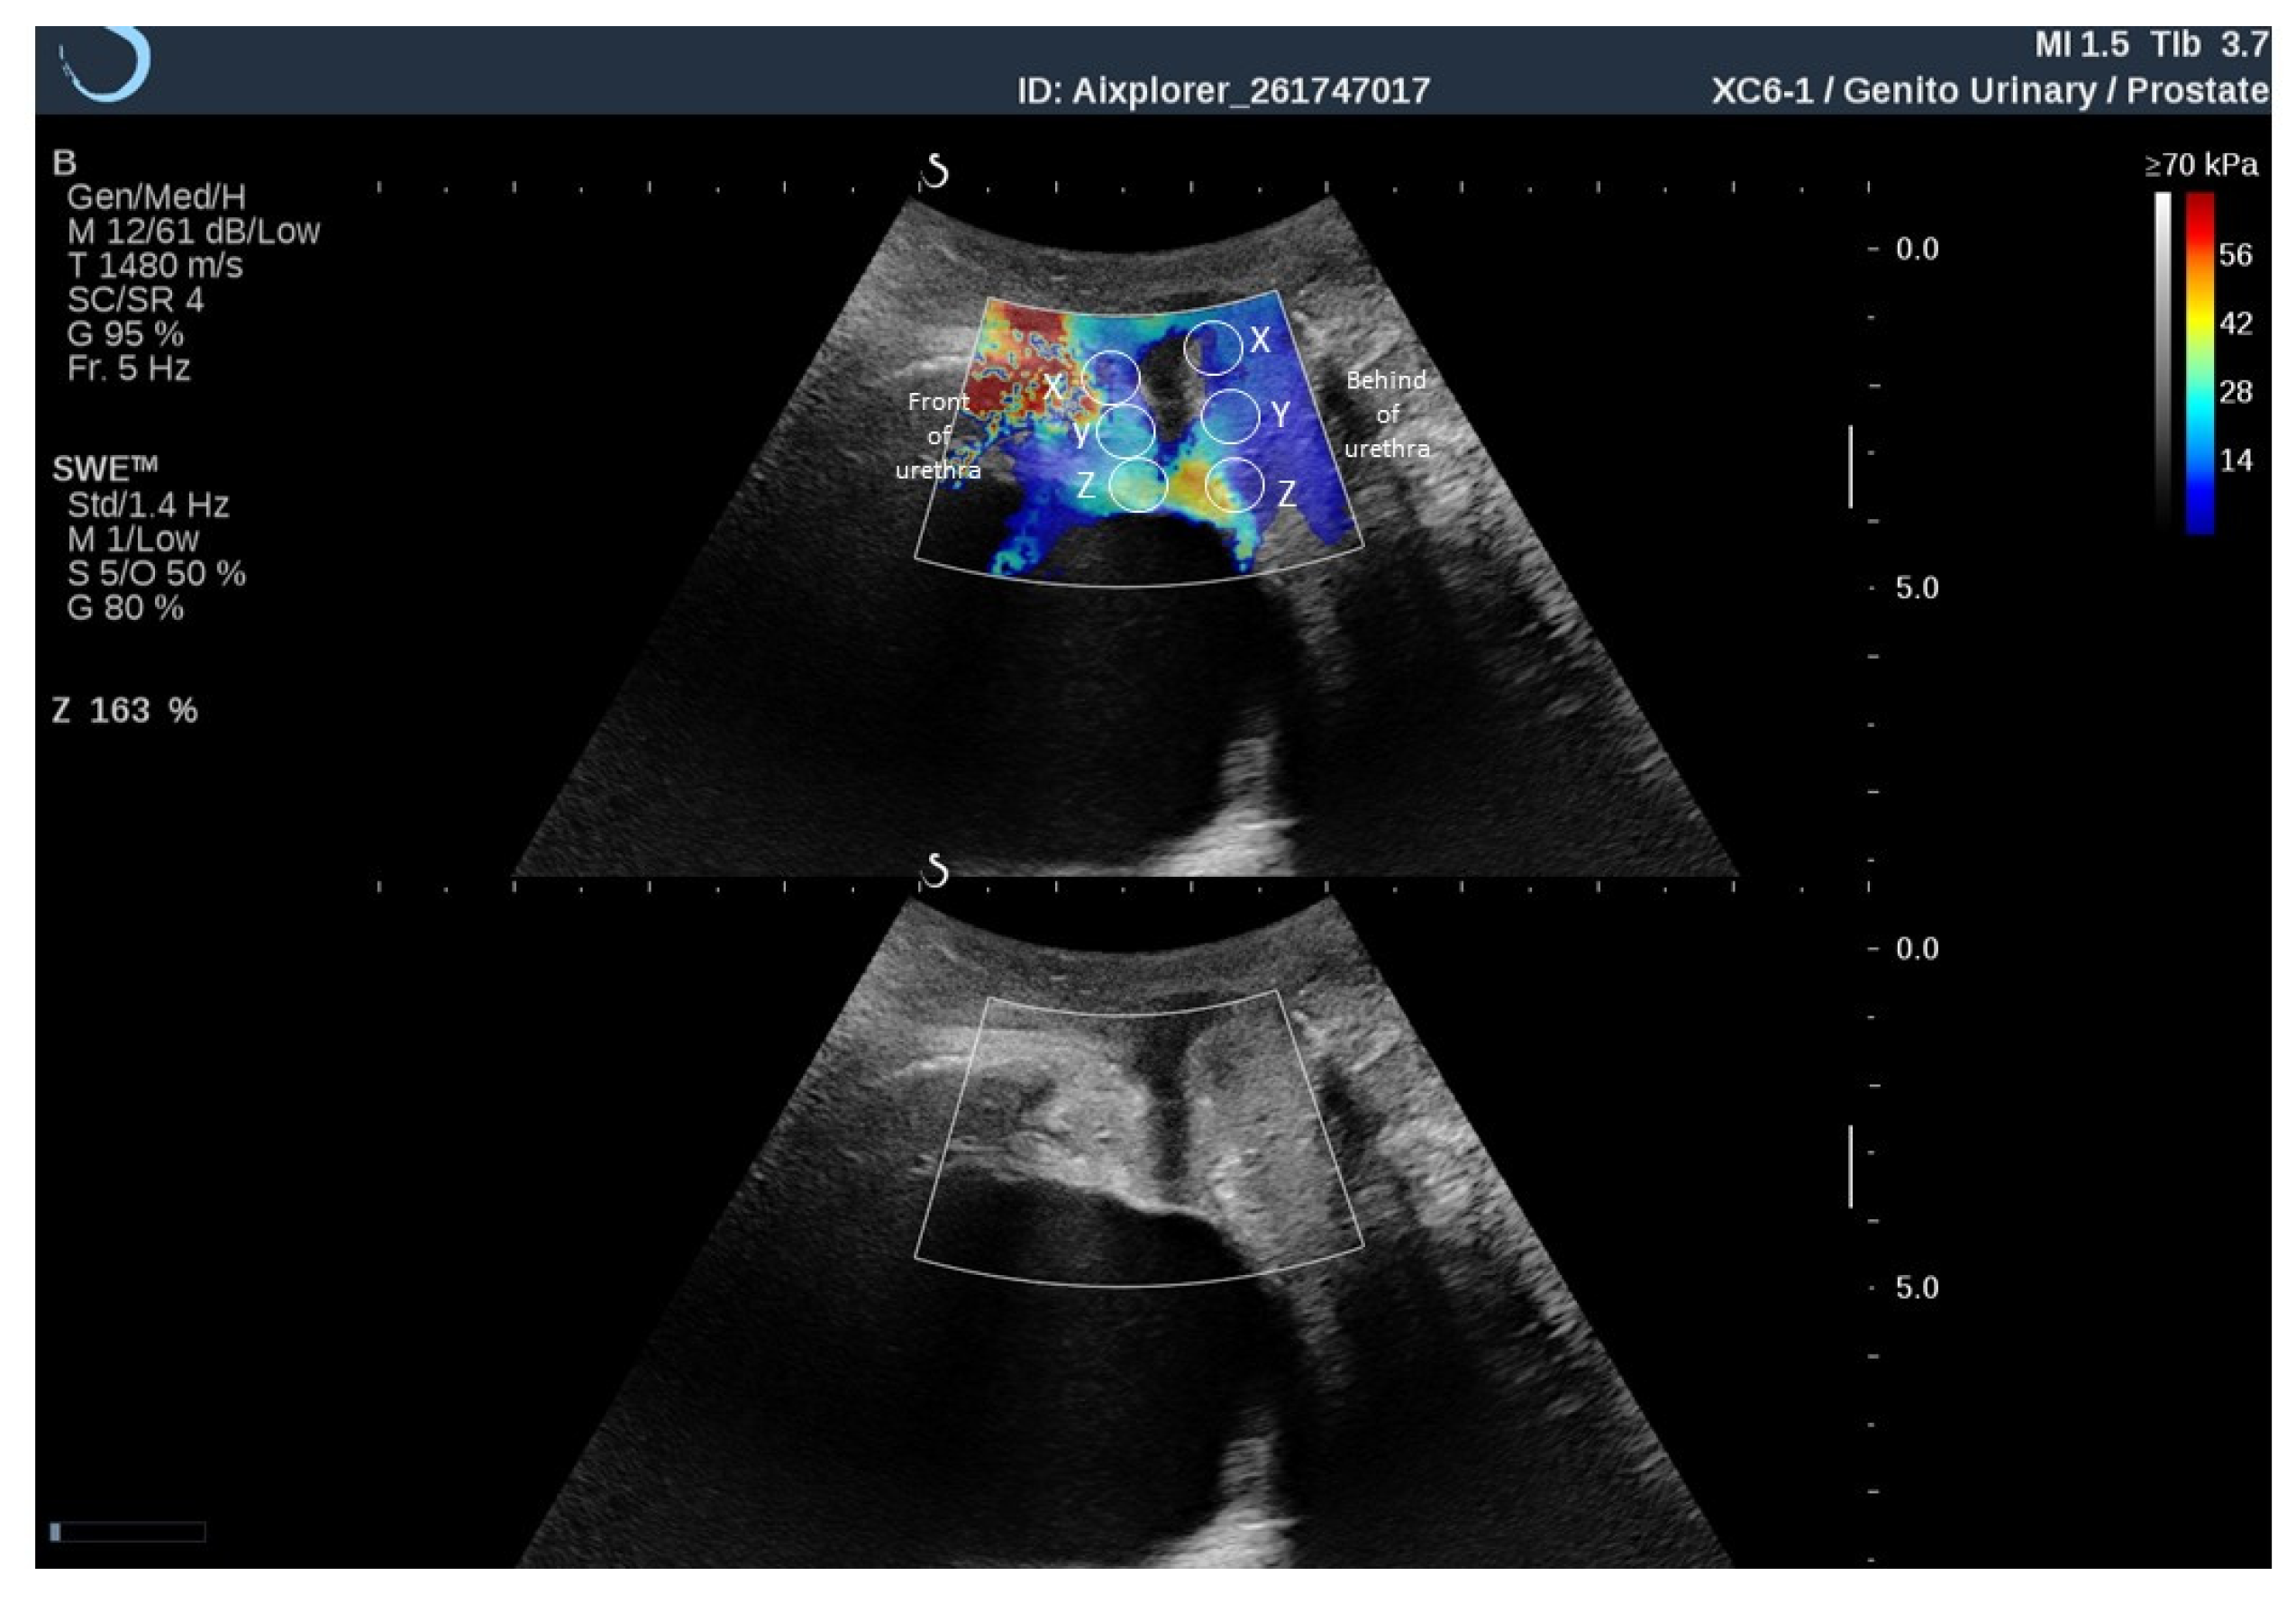

| Q-Box | Rest Tone of PFM (kPa) | Contraction of PFM (kPa) | p-Value * | |||

| Front of urethra | X | 11.9 | 6.9–17.0 | 35.0 | 25.0–43.3 | 0.002 |

| Y | 15.1 | 9.9–20.0 | 35.9 | 28.0–51.0 | 0.001 | |

| Z | 15.0 | 10.3–17.0 | 18.5 | 15.0–28.0 | 0.024 | |

| Behind of urethra | X | 10.9 | 9.3–17.6 | 14.5 | 10.2–16.5 | 0.91 |

| Y | 11.2 | 8.7–14.0 | 10.8 | 9.4–15.5 | 0.89 | |

| Z | 12.0 | 8.8–15.0 | 12.6 | 9.0–14.0 | 0.63 | |